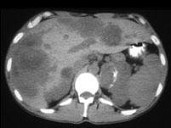

- 多项选择题男,37岁, 阵发性高血压1月余,结合所示图像, 最可能的诊断是 ( )

A、左侧肾上腺癌

B、左侧恶性嗜铬细胞瘤

C、左侧肾上腺转移癌

D、肝转移癌

E、原发性肝癌